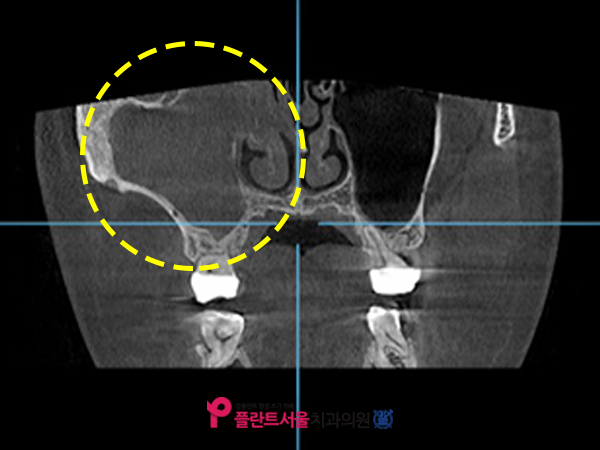

CT사진

노란색으로 표시된 부분은 인공치아를 심을 때 뼈를 이식하는 상악동입니다. 반대쪽과 비교했을 때 뭔가 꽉 차있는 게 보이죠? 콧물이나 고름, 점액질을 비롯한 각종 이물질들이었어요.

코 막힘이나 콧물이 나오고 있는 증상이 있다고 말씀을 하셨는데. 앞서 말씀드렸듯이 축농증으로 인해 비어 있어야 할 공간에 이물질이 가득 차게 되면 상악동을 들어올리는 과정에서 천공이 발생할 수 있으며, 공간 확보가 제대로 되지 않아 픽스처를 식립하기가 어려울 수 있습니다.

인공치근 주변에서 2mm 이상의 뼈를 만들어야 하는데, 이렇게 내부에 쌓여있는 이물질의 압력으로 인해 안전하게 식립이 어려운 것이죠. 만약 해당 부위에 무리하게 인공치아를 심을 경우 천공 이외에도 나중에 보철치가 흔들리거나 탈락될 수 있고 여러 합병증이 발생할 수 있으므로 본원은 가장 먼저 축농증을 완화시킨 후 골이식 임플란트를 진행하는 치료계획을 수립하였습니다.